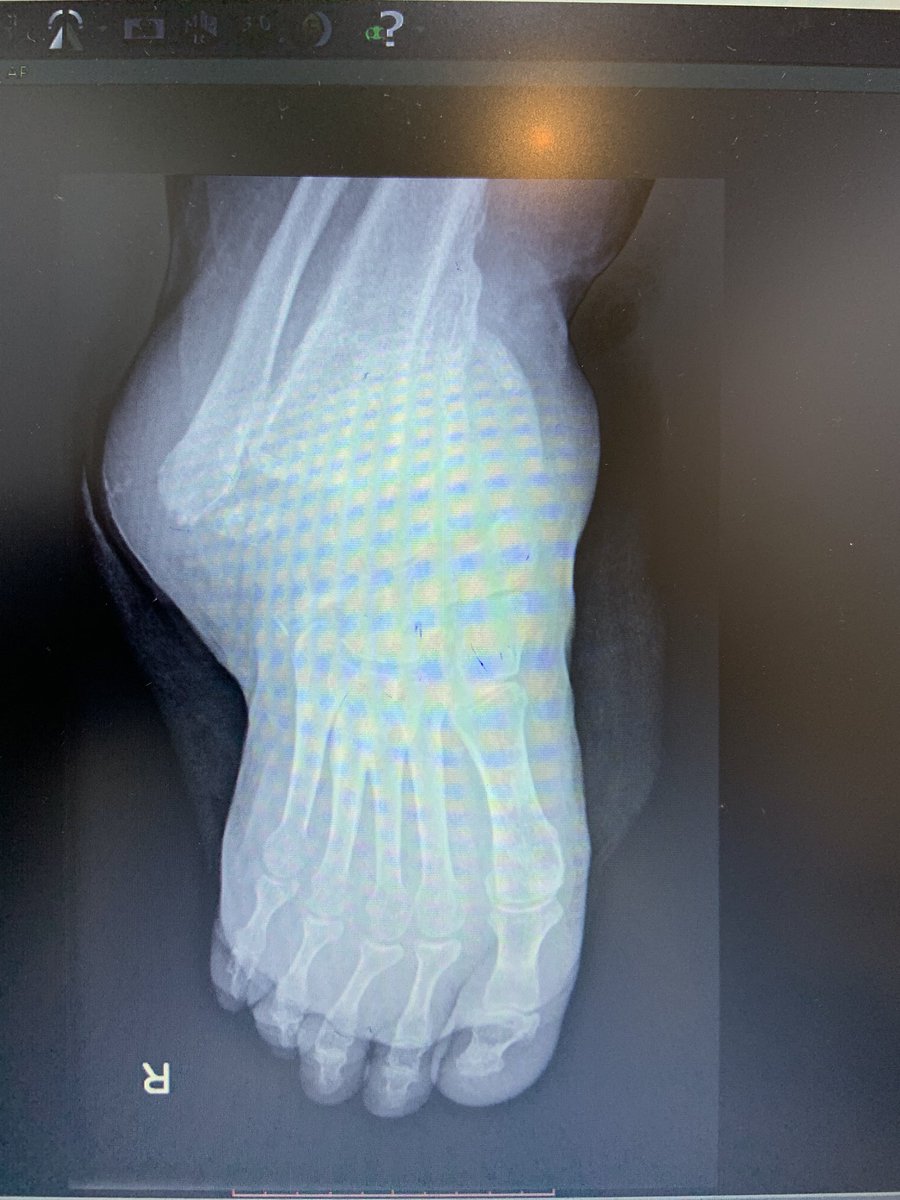

هي عبارة عن كسور تصيب القدم السكرية نتيجة اعتلال الأعصاب الطرفية السفلية وفقدان الإحساس.وتختلف تماما عن الكسور العادية.

غالباما يسبق حدوث قدم شاركوت إصابة بالقدم أوالكاحل ونظرا لضعف الإحساس في القدم ، مريض السكر يستمر بالمشي على قدمه مما يؤدي الى تكسر في عدة عظام أو خلع في المفاصل.

إذا تم التشخيص في مرحلة مبكرة قبل حدوث تكسر في العظام أو خلع في المفاصل فنسبة المحافظة على القدم تكون عالية وتقلل نسبة المضاعفات.

الأعراض المبدئية لقدم شاركوت تشمل تورم، احمرار وألم في القدم أو الكاحل وغالبا الأشعة السينية تكون سالبة في هذه المرحلة، ونظرا لقلة خبرة الأطباء بقدم شاركوت فلا يتم التشخيص المبكر. وغالبا يصل المريض الى الطبيب المختصص في مرحلة متأخرة.